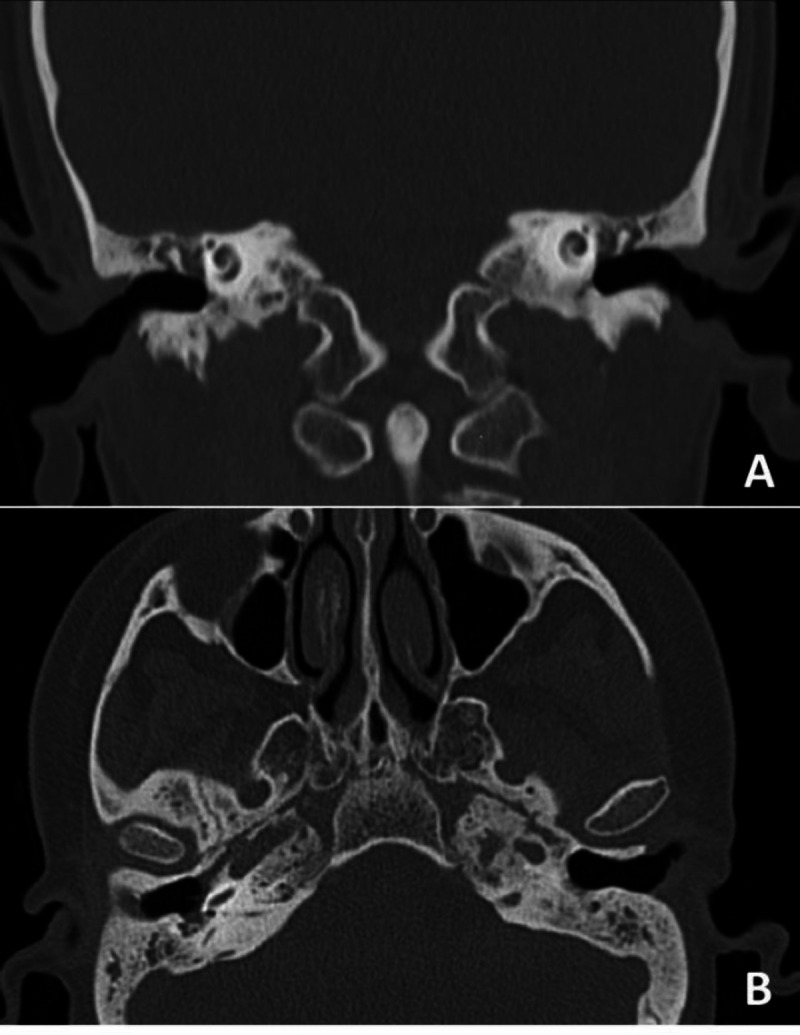

Introduction: Ear symptoms of granulomatosis with polyangiitis can range from ear fullness and otalgia to conductive or sensory neural hearing loss and sudden deafness. Cochlear implantation in these patients faces two challenges: access to the round window and control of mastoid and middle ear inflammation. The combined approach in cochlear implantation is a classic trans-facial recess approach facilitated by a trans-canal view.

Case report: In this case report, we present the "combined approach" in a 20-year-old lady with granulomatosis with polyangiitis who underwent cochlear implantation successfully using the combined approach.

Conclusion: Post-operative results suggest that the "combine approach" seems to be a safe, easy, and fast cochlear implantation technique for chronic otitis media with an atelectatic middle ear and retracted tympanic membrane or narrow facial recess space. It is a single-stage surgery that has no need for the obliteration of the ear and has less morbidity.